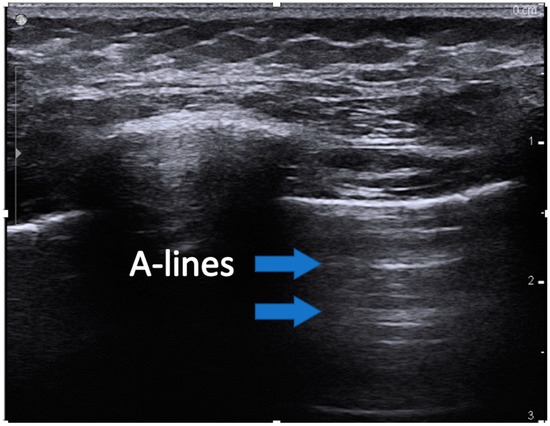

- A-lines are horizontal artifacts produced by air in the chest cavity. Air reflects ultrasound waves and prevents the visibility of structures beneath. Some of the reflected ultrasound waves, however, bounce back and forth between the muscle, and fascia of the chest wall and return to the transducer, generating reverberation artifact called a-lines (Figure 1).

Figure 1. Image showing an example of A-lines. The blue arrows indicate the reverberation artifact lines at recurring regular intervals. - (4)